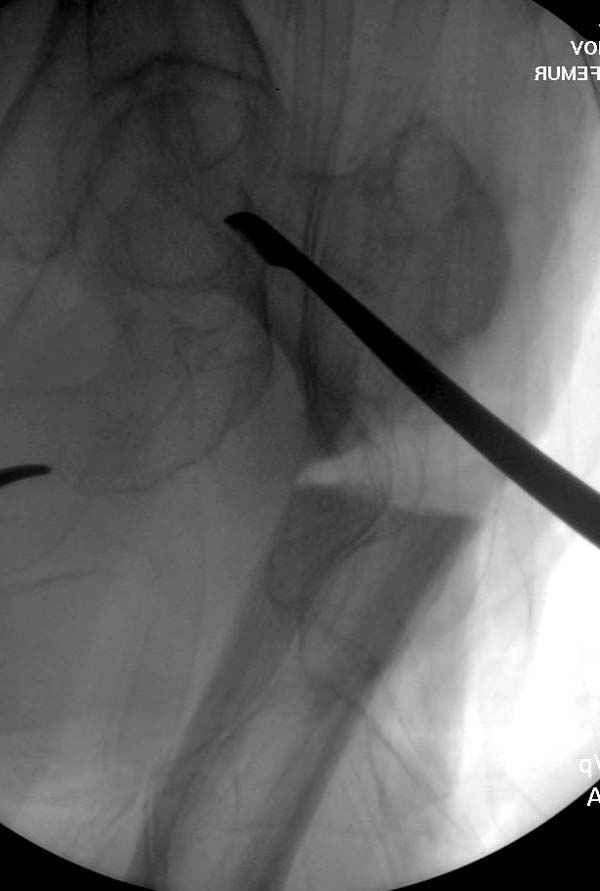

Страйкер предоставил отличный инструмент - крючок для удаления длинного гвоздя. Считаем, что врачебная ошибка по установке привела к несостоятельности импланта и к ятрогенному осложнению.